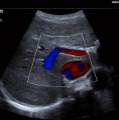

ACUSON P500 Ultrasound System

●可攜式超音波儀器隨時隨地提供高品質影像成像